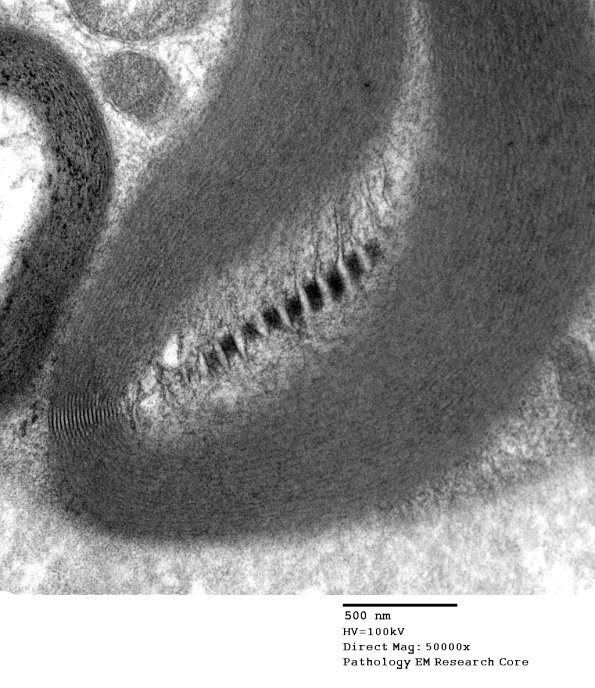

Higher magnification of image #4B1. (electron micrograph)